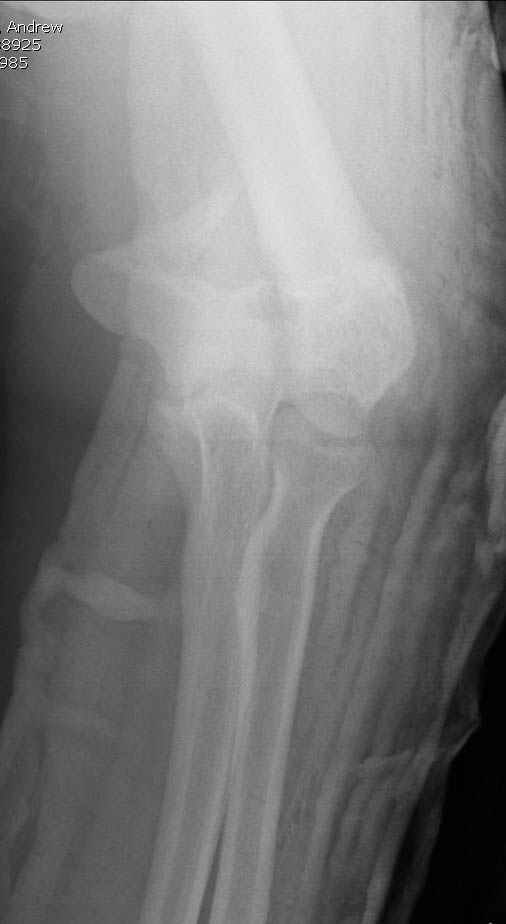

Уважаемые коллеги! Мужчина, 28 лет. 1 сутки назад получил бытовую травму - закрытый чрезмыщелковый перелом правой плечевой кости со смещением. По месту жительства в ЦРБ - репозиция, иммобилизация. Направлен к нам.

Солидарен с мнением обоих Александров (Челнокова и Рыкова): точную репозицию такого перелома вряд ли удастся выполнить закрыто. Даже во время открытого вмешательства это сделать непросто. Неслучайно предложен костно-пластический доступ с временным отсечением локтевого отростка. И по методу фиксации согласен с Александром Челноковым: 2 пластины. В качестве примера привожу рентгенограммы одного из наших пациентов с аналогичным повреждением.

С уважением, А. Золотов, Приморский край.